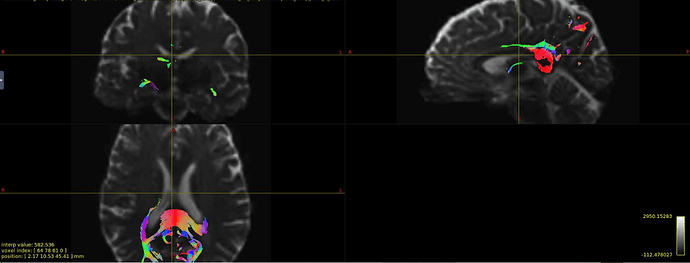

Interesting… From the coronal slices it seems like there are other WM regions devoid of tracks, such as the uncinate fasciculus. The missing part of the corpus callosums suggests that the tapetum is missing, too, which also goes to the temporal lobe. There may be something off in the diffusion data in the temporal lobes. What happens if you seed the missing region in the corpus callosum?

Thanks for your response! If I seed from the missing regions, I still see a similar pattern. I’ve also tried changing the -angle option from the default to 70 and 80, and the -step option to .2 and .08, and the same pattern persists. Since my CSD data looks normal, I’m thinking that maybe the tensor algorithm is undertracking certain regions.

It’s hard to tell from the small images, but it seem counterintuitive that a seed region would have zero streamlines going through it… unless the underlying data does not support a streamline. Can you post an image of your FA map and zoom in the callosum? Maybe there is a big hole of FA values in that region.

Yes, I can post the FA maps! I also thought that it was weird that there were no streamlines from the corpus callosum, but the FA maps look okay.